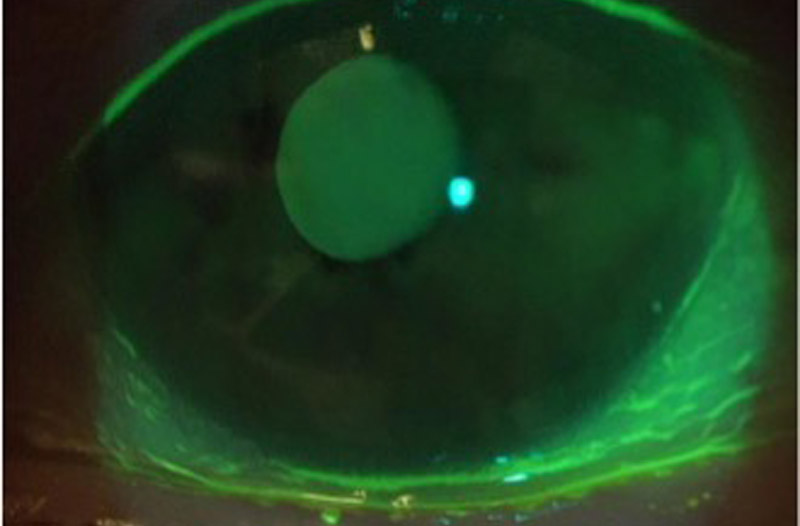

涙が少ししか溜まっていません。

涙の量は改善しました。

目頭にチューブが入っています。